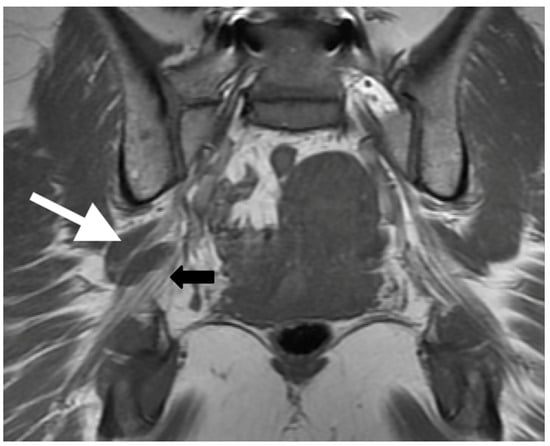

Variant sciatic nerve anatomy also showed a statistically significant (p = 0.01) increased rate of T2-signal abnormality (63.0% variant vs. 43.0% normal). In both groups, the signal abnormality occurred at, or just distal to, the greater sciatic foramen, possibly reflecting the most vulnerable site for nerve entrapment or compression. Furthermore, regardless of variant sciatic nerve type, increased nerve T2 signal strongly correlated with the symptomatic side (98.0%). Figure 5 illustrates this finding, with bilateral type II variant split sciatic nerves in a patient who presented with symptoms on the left side, wherein increased signal was demonstrated only on the left (symptomatic) side. Although only a minority of variant and normal nerves displayed an asymmetric nerve caliber or asymmetric piriformis size (hypertrophy or atrophy), both imaging findings were significantly associated with the symptomatic side (98.0%). A detailed evaluation of variant anatomy is therefore essential for an accurate diagnosis.

Figure 5.

Patient presented with left-sided symptoms and lumbosacral plexus MRN showing bilateral type II variants: (a) coronal T1-weighted sequence showing right-sided sciatic nerve split around the normal right (white arrow) and atrophied left (yellow arrow) piriformis muscle; (b) coronal STIR sequence demonstrating increased signal of the left sciatic nerve (red arrow).